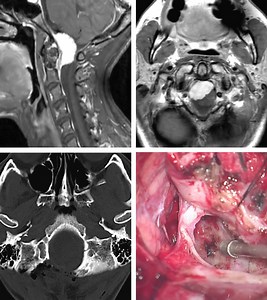

Anatomy - Vinko

Rozic - Medial Approach